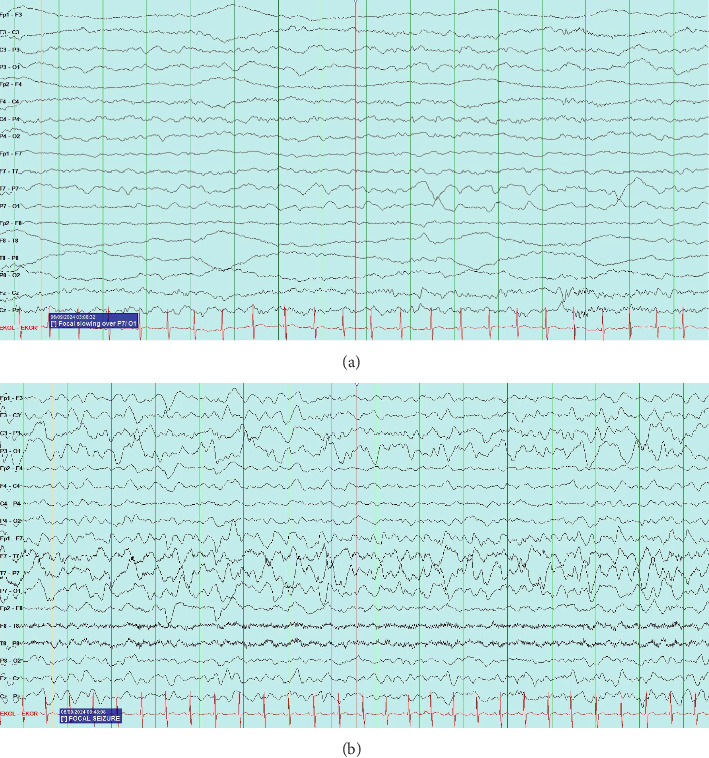

Sturge-Weber Syndrome (SWS), also called encephalotrigeminal angiomatosis, is a rare congenital neurological condition classified by the hallmark findings of a port-wine birthmark, leptomeningeal angiomas, and glaucoma. Here, we present a case of a two-year-old patient with a history of a left-sided port-wine birthmark involving the V1-V2 dermatomes who re-presented to the emergency department with focal right-sided seizure-like activity in the setting of a recent head trauma. The patient was admitted for further workup, where video electroencephalography demonstrated the presence of electrographic seizures developing from the left posterior quadrant, with continuous focal slowing over the left hemisphere, and with magnetic resonance venography revealing findings concerning for a pial angiomatosis. This finding, coupled to new-onset seizure-like activity in a patient with a port-wine birthmark, supported a diagnosis of SWS. He was started on an antiepileptic drug regimen with resolution of seizure-like activity while inpatient and his subsequent care was transferred to a specialized clinic designed to manage patients with SWS. Most patients diagnosed with SWS exhibit seizure-like activity, often presenting as infantile spasms, within the first year of life; our patient, on the other hand, began to exhibit focal seizures following a traumatic event and was later found to harbor findings consistent with SWS. Overall, this case highlights the role of a multidisciplinary team in the management of patients with SWS and demonstrates the importance of routine follow-up testing, imaging, and subspecialty care for these patients.